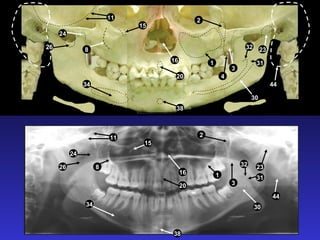

2. Các mốc giải phẫu trên phim toàn cảnh

1. Xoang hàm

2. Hố chân bướm hàm

3. Xương chân bướm

4. Gai bướm

5. Cung xương gò má

6. Lồi khớp xương thái dương

7. Đường khớp gò má thái dương

8. Mỏm gò má

9. Lỗ ống tai ngoài

10. Mỏm chũm

11. Hố sọ giữa

12. Bờ viền ngoài ổ mắt

13. Bờ dưới ổ mắt

14. Lỗ dưới ổ mắt

15. Ống dưới ổ mắt

16. Hốc mũi

17. Vách ngăn mũi

18. Gai mũi trước

19. Xương cuốn dưới

20. Lỗ răng cửa

21. Vòm miệng cứng

22. LồI củ xương hàm trên

23. LồI cầu

24. Mỏm vẹt

25. Khuyết sigma

26. Hố giữa khuyết sigma

27. Mỏm trâm

28. Cột sống cổ

29. Gờ chéo ngoài

30. Ống răng dưới

31. Lỗ ống răng dưới

32. Gai Spix

33. Lỗ cằm

34. Hố tuyến dưới hàm

35. Gờ chéo trong

36. Hố cằm

37. Gờ cằm

38. Gai cằm

39. Xương móng

40. Lưỡi

41. Vòm miệng mềm

42. Lưỡi gà

43. Thành sau họng

44. Dái tai

45. Khoang lưỡi hầu

46. Khoang mũi hầu

47. Khoang vòm miệng lưỡi